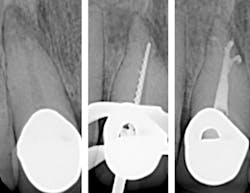

Switching to motorized shaping and carrier-based obturation increases speed and efficiency, which outweighs any addition material cost. The end result is satisfied patients, increased referrals, and greater production. When deciding a file system to streamline the shaping process, the WaveOne system allows for a simplified technique. This system permits deep apical shapes that can accommodate irrigating syringes in the apical third of the canal system. This is the most critical zone of disinfection. Once irrigated, three-dimensional obturation can be quickly and effectively completed with the GuttaCore System. This allows the dentist to deliver heated gutta-percha throughout the canal system, which can result in impressive outcomes. (See photo.)